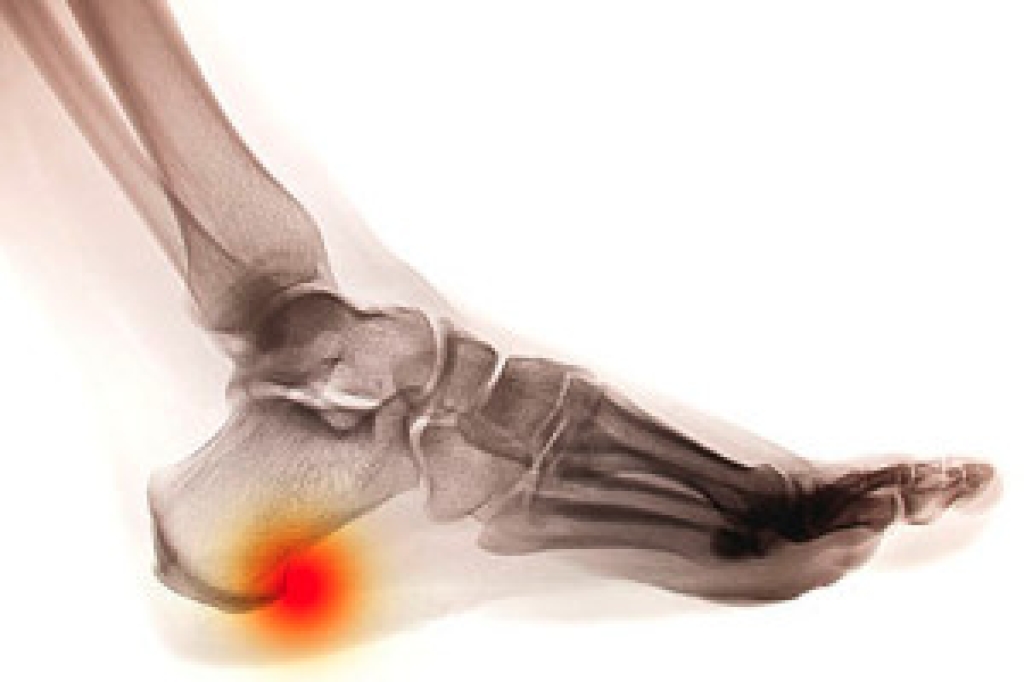

Heel spurs are bony outgrowths at the base of the heel bone, and implementing targeted exercises is a proactive approach to managing heel spur pain. Stretching exercises, such as towel curls and toe stretches, help maintain flexibility in the foot's connective tissues, mitigating strain on the heel. Calf stretches, performed against a wall, alleviate tension in the Achilles tendon, and may help to reduce the impact on the heel spur. Rolling a frozen water bottle under the foot not only provides relief but also minimizes inflammation. Incorporating these exercises into a regular routine can contribute to the gradual alleviation of heel spur discomfort. It is imperative to approach these exercises with patience, allowing the body time to adapt and heal. Consultation with a podiatrist is advisable to tailor exercises to individual needs. If you have developed a heel spur, it is suggested that you schedule an appointment with a podiatrist who can effectively diagnose and treat this condition.

Heel spurs are formed by calcium deposits on the back of the foot where the heel is. This can also be caused by small fragments of bone breaking off one section of the foot, attaching onto the back of the foot. Heel spurs can also be bone growth on the back of the foot and may grow in the direction of the arch of the foot.

Older individuals usually suffer from heel spurs and pain sometimes intensifies with age. One of the main condition's spurs are related to is plantar fasciitis.

The pain associated with spurs is often because of weight placed on the feet. When someone is walking, their entire weight is concentrated on the feet. Bone spurs then have the tendency to affect other bones and tissues around the foot. As the pain continues, the feet will become tender and sensitive over time.